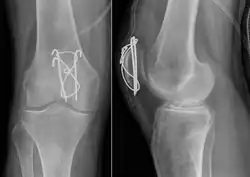

Most patella fractures are transverse or comminuted, hence the quadriceps mechanism is disrupted and they are treated by a combination of wires in a tension band construct. This unites the fractured bones, reconstructing the straightening mechanism of the leg.[5][6]